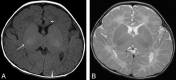

Fig 2.

Type 2. White matter abnormalities, especially around the trigones. FLAIR image of a 4-year-old patient (case 22) (A) with an ATRX mutation of the chromatin-remodeling domain in exon 19 (p.V1624M), and a 35-month-old patient (case 21) (B) with an ATRX mutation of the chromatin-remodeling domain in exon 19 (p.A1622V). Increased signal intensity on T1WI/FLAIR in the periventricular region, especially around the peritrigonal area (arrow), and enlargement of perivascular space (arrowhead) are seen.